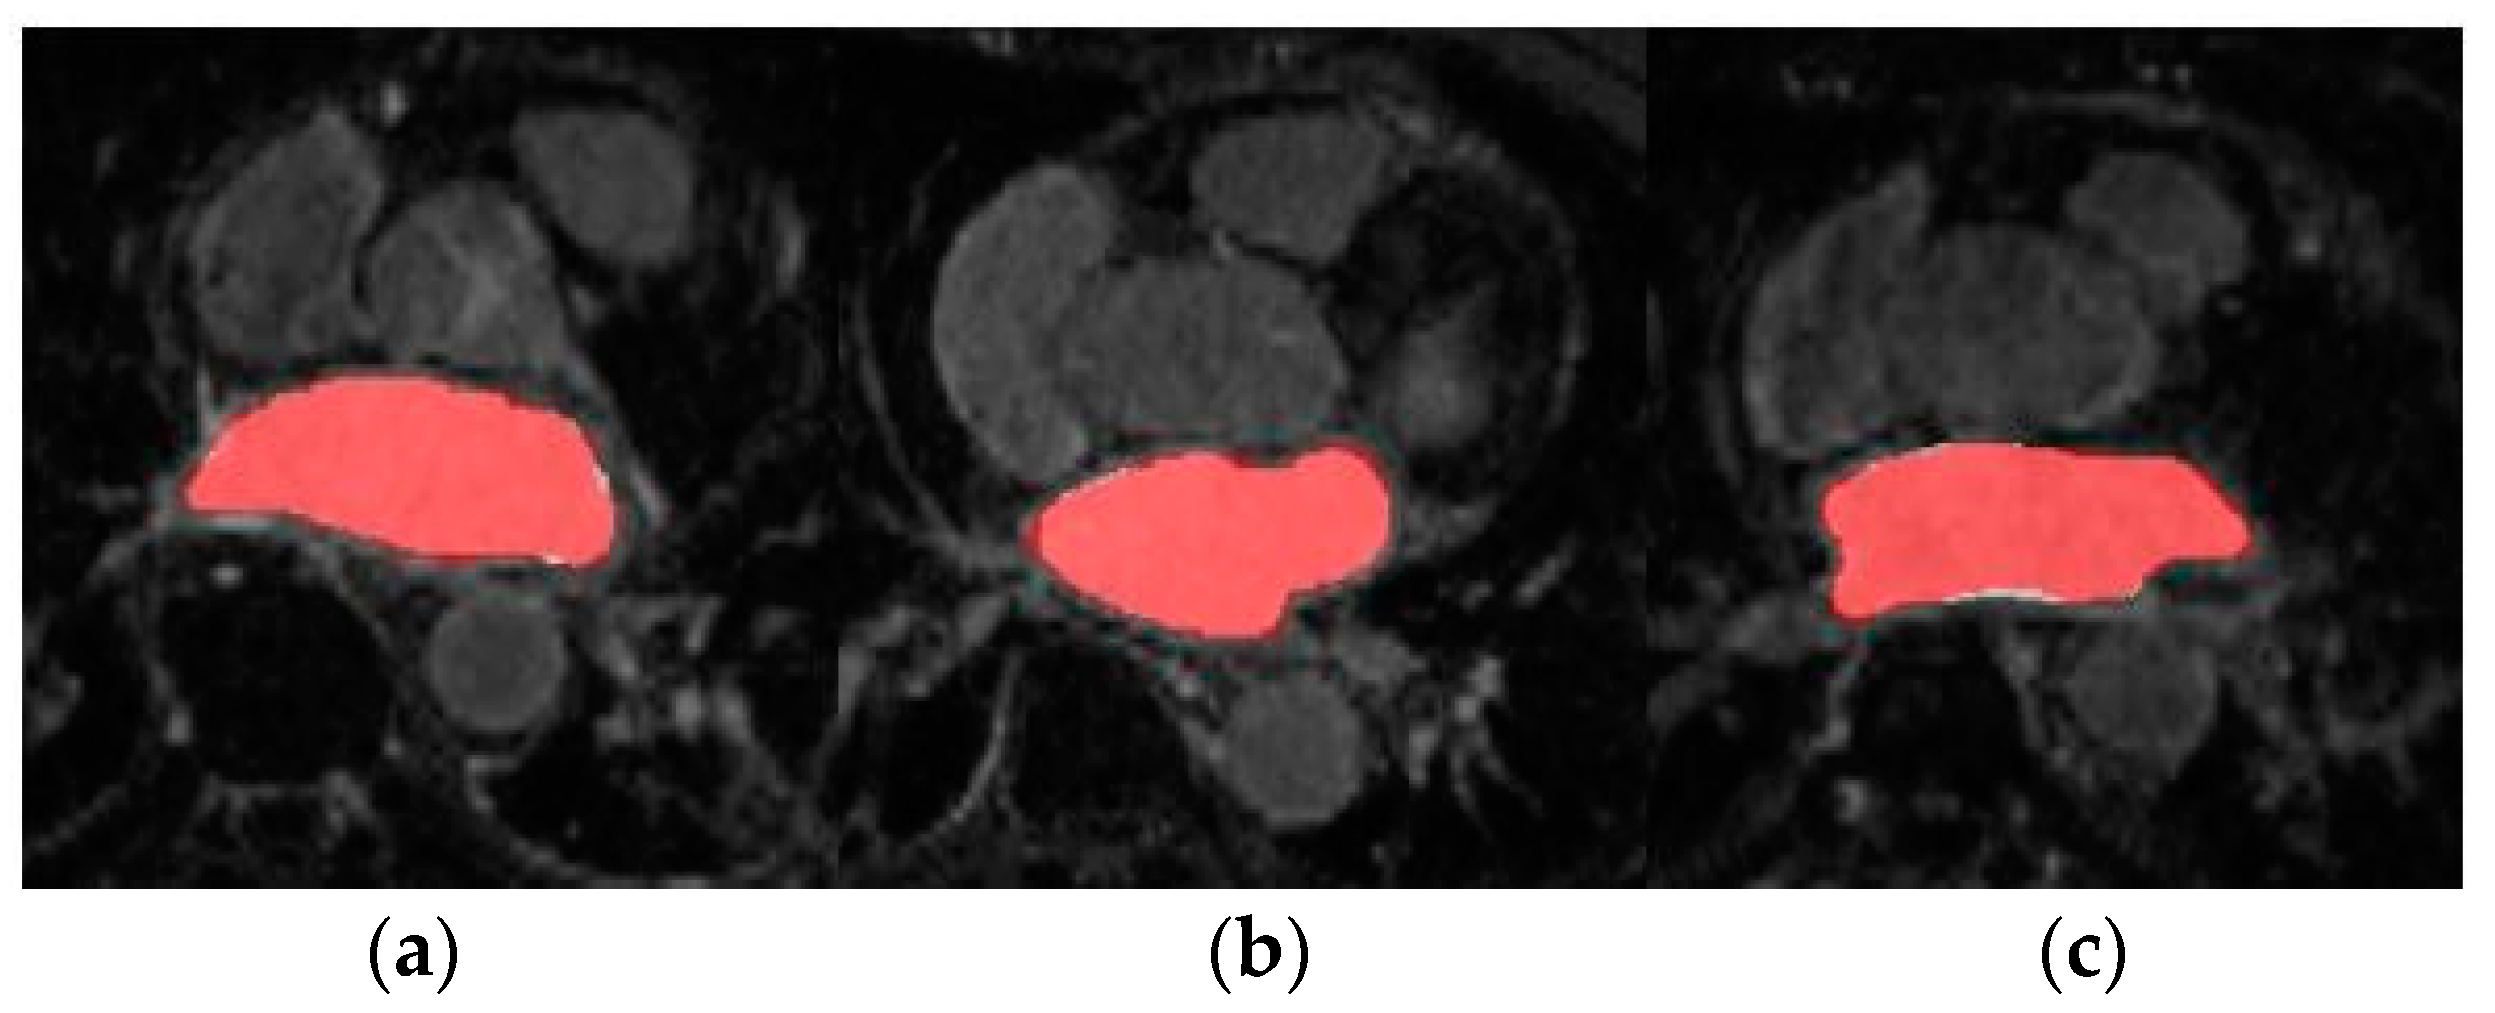

Figure 6 shows the axial view of predictions obtained for three representative testing patients (and slices) of Database 3 with the different trained models for RA segmentation.

Due to the absence of previous works that employ Database 3 solely as an external validation dataset, we are not able to compare the generalization ability of our proposed model. On the other hand, a visual representation of the increased performance of the models with SDA can be seen in Figure 5 and Figure 6 for LA and RA segmentation tasks, respectively. As we can observe, the blood pool prediction segmentation of the LA and RA performs best in the SDA model.

Figure 6. From left to right, axial slice of RA segmentations in networks w/o SDA (left) and w-SDA (right) for 3 patients (ac).